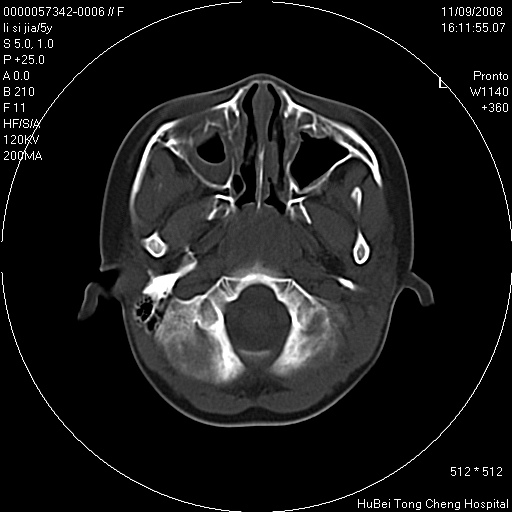

患儿 女,5岁。鼻塞、流涕2年余。

临床诊断:慢性副鼻窦炎?

副鼻窦ct轴位平扫(层厚、层距均为5mm),图像如下:

双侧上颌窦\\筛窦及蝶窦内均可见多量软组织密度影,结合病史支持考虑慢性全鼻窦炎

双侧上颌窦、筛窦及蝶窦内均可见粘膜增厚,结合病史支持考虑慢性全付鼻窦炎,腺样体肥大。